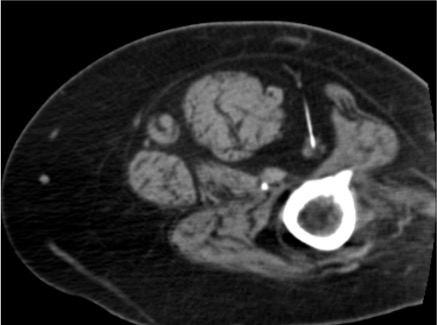

- Subgluteal space: runs between greater trochanter (lateral) and ischial tuberosity (medial) under gluteus maximus — optimal CT-guided access point

- Subgluteal approach: needle targets perineural fat between greater trochanter (lateral) and ischial tuberosity (medial), posterolateral to sciatic nerve

- Sciatic nerve appears as elliptical structure with internal fascicular architecture (fascicles visible on CT) in the perisciatic fat

- Proximal approach (ischial spine level): larger nerve cross-section; more predictable spread; used for oncologic or high-level entrapment